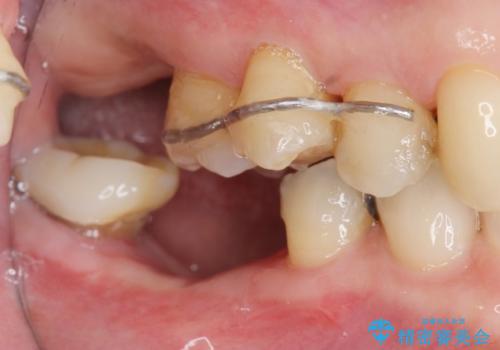

部分矯正を含む 歯周病治療 (再生治療・歯周ポケット除去・MTM・連結補綴)

検査の結果、強い歯ぎしりによる歯の周囲の骨の吸収が認められたため歯槽骨の再生・歯周ポケットの除去・力に対抗する連結補綴・補綴前処置としての小矯正を計画します。

今回連結補綴を行うにあたり、歯周病の問題を解決するために再生療法・歯周ポケット除去手術を、またより歯の神経を保存し力に対抗できる環境を整えるために小矯正を行い精度の高いメタルボンドクラウンを製作することができました。